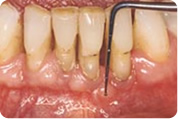

Uznapredovali paradontitis - ireparabilno oštećenje potpornog tkiva i okolne kosti, džepovi su duboki preko 6 mm i krvare, hranjenje je otežano, slab zadah je konstantan, loše opće stanje, vjerojatan gubitak zuba.